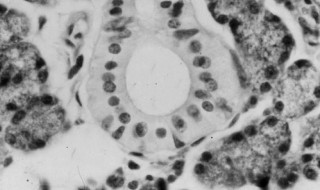

2、常见的形式是,腺泡主要由黏液性腺细胞组成,几个浆液性腺细胞 位于腺泡的底部或附于腺泡的末端,在切片中呈半月形排列, 故称半月。

3、半月的分泌物可经黏液性细胞间的小管释入腺泡腔内。